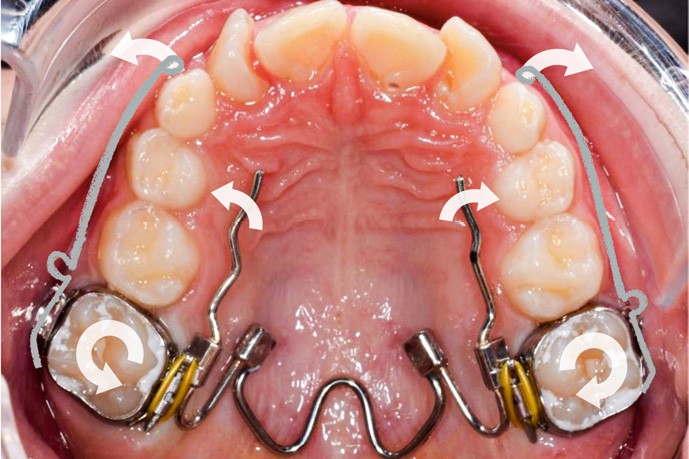

Des bagues molaires sont essayées et adaptées sur 16 et 26 et un arc transpalatin à mémoire de forme (Nitanium Palatal Expander -Ortho Organizers, USA) dont la dimension est sélectionnée à partir de la mesure de la distance inter-molaire mandibulaire est ligaturé à celles-ci hors bouche. L’ensemble est scellé avec un ciment verre-ionomère après refroidissement au spray à -45 °C de la partie en NiTi pour insertion facilitée.

Trois jours plus tard, des bras en TMA .017 x .025 habillés d’une gaine de protection avec omega au contact des tubes des premières molaires et dont l’extrémité mésiale forme une boucle sont ligaturés aux dispositifs collés de traction.

Une fois que la partie en alliage à mémoire de forme de l’arc transpalatin a retrouvé sa forme initiale, l’arc est désinséré. Les U latéraux et les lames d’insertions en acier sont réglés dans les trois sens de l’espace à l’aide d’une pince 139 pour corriger l’inclinaison mésio-distale, le torque et augmenter la dérotation de 16 et 26 pour assurer une traction supplémentaire des canines incluses en direction vestibulaire. Les bras d’expansion des secteurs latéraux de l’arc transpalatin sont également sectionnés. Les bras vestibulaires en TMA sont activés dans le sens vertical pour une traction des canines vers le plan occlusal.